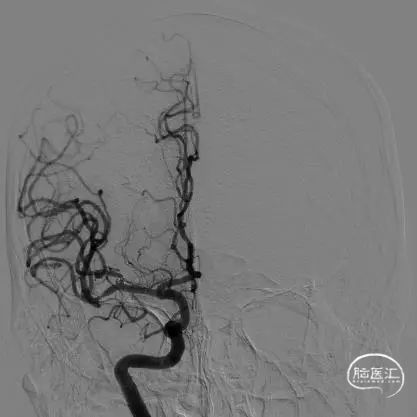

DSA结果:右侧大脑中动脉分叉部动脉瘤,大小约:2.2mmx1.7mm、瘤颈:约2.6mm,未破裂型。

术前影像

术后影像

术后即刻正侧位造影示:动脉瘤内无造影剂滞留,Raymond分级:3A级。